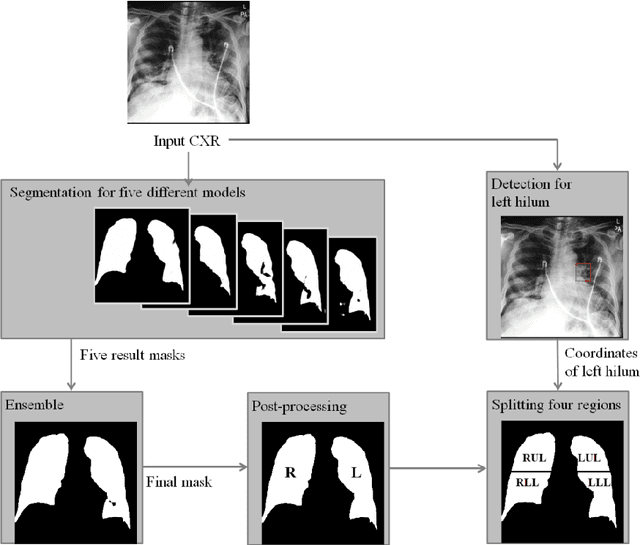

Purpose. Imaging plays an important role in assessing severity of COVID 19 pneumonia. However, semantic interpretation of chest radiography (CXR) findings does not include quantitative description of radiographic opacities. Most current AI assisted CXR image analysis framework do not quantify for regional variations of disease. To address these, we proposed a four region lung segmentation method to assist accurate quantification of COVID 19 pneumonia. Methods. A segmentation model to separate left and right lung is firstly applied, and then a carina and left hilum detection network is used, which are the clinical landmarks to separate the upper and lower lungs. To improve the segmentation performance of COVID 19 images, ensemble strategy incorporating five models is exploited. Using each region, we evaluated the clinical relevance of the proposed method with the Radiographic Assessment of the Quality of Lung Edema (RALE). Results. The proposed ensemble strategy showed dice score of 0.900, which is significantly higher than conventional methods (0.854 0.889). Mean intensities of segmented four regions indicate positive correlation to the extent and density scores of pulmonary opacities under the RALE framework. Conclusion. A deep learning based model in CXR can accurately segment and quantify regional distribution of pulmonary opacities in patients with COVID 19 pneumonia.